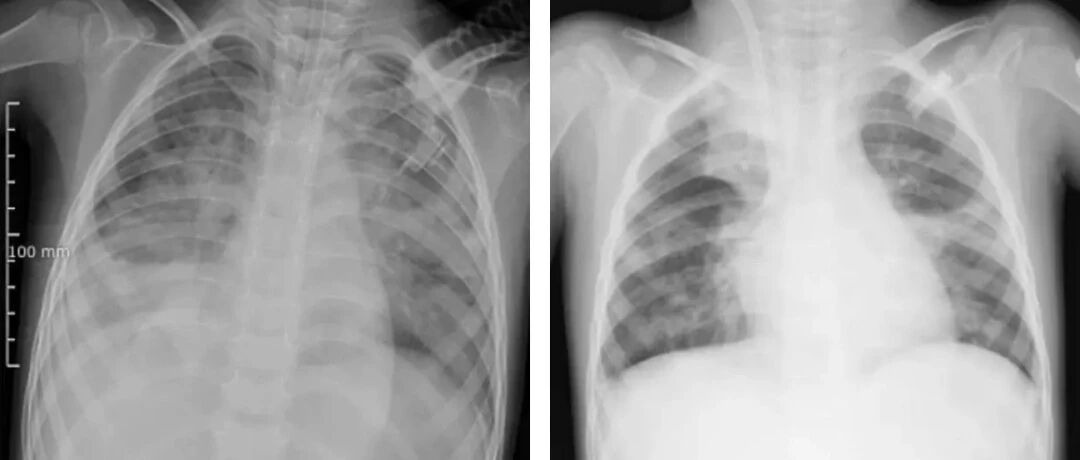

呂艷玲提醒,如果咳嗽持續時間超過一周甚至達到10天,務必及時做胸部CT檢查,排除合并肺炎的可能。即使燒退了,也不能掉以輕心,以免延誤病情。除了及時診治,主動預防也至關重要,科學接種疫苗,降低感染風險。